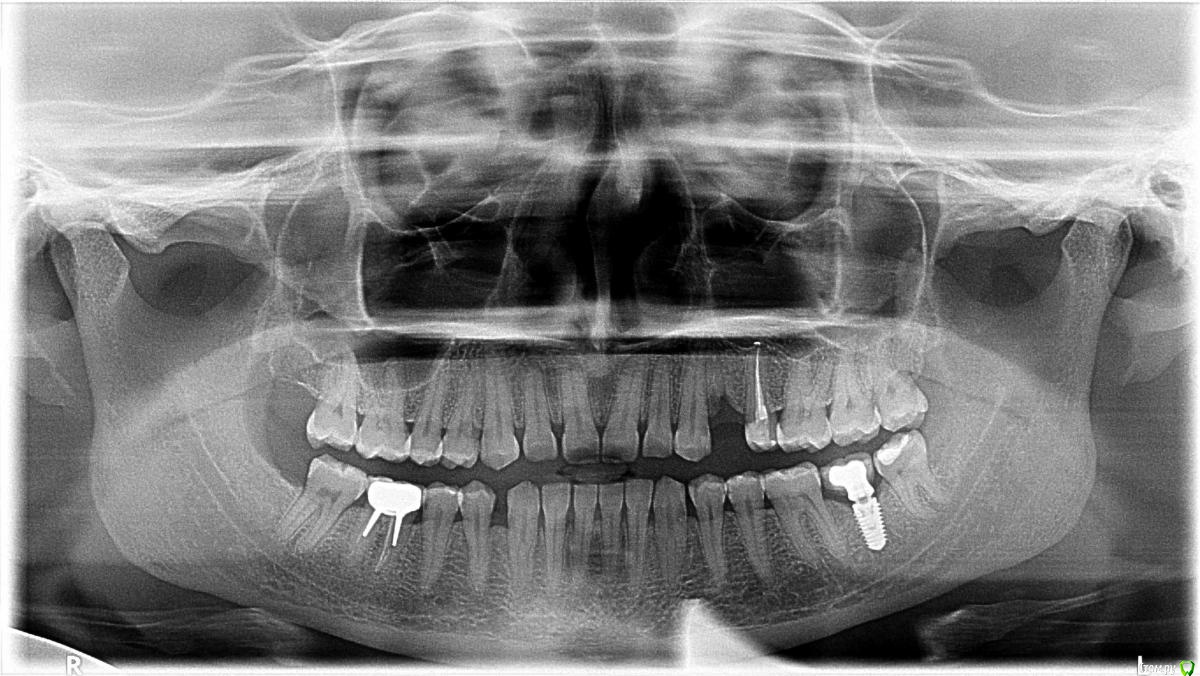

АннаПетровна Опубликовано 1 июня, 2019 Поделиться Опубликовано 1 июня, 2019 Здравствуйте, уважаемые стоматологи!!У меня прижился имплант, но провалилась уже вторая попытка поставить коронку, так как появляются боли.Расскажу в подробностях.Марка MEGAGEN AnyRidge, Южная Корея. Поставили 10 апреля 2018 на месте 37 зуба. Сразу болело около 10 дней. Всё это время я пила антибиотики, потом через месяц где-то повторяла антибиотики по причине боли после пломбирования каналов зуба №25, ибупрофен принимала первые 2-3 дня, потом ещё два раза с перерывами, 1 раз - т.к. десна слегка была опухшая мне врач назначил, 2 раз - после пломбирования каналов зуба. Что касается лечения зуба №25 почти совпавшего по времени. Мне поменяли пломбу в этом зубе перед имплантацией, т.к. одновременно планировалось имплантировать 2 зуба: 37 и 24, то есть по-соседству. И №25 стал болеть, потом пломбу поменяли ещё раз он продолжал болеть. Но меня успокоили, что ничего страшного, можно ставить импант. Но я решила ставить только 1 имплант, который не по соседству. Как стало известно позже, у меня уже некротизировался нерв, но этого не знали. Поскольку зуб продалжал болеть, ещё после месяца мучений после импланта, его депульпировали. Потом запломбировали каналы, получился выход материала за пределы корня (чего не было видно на снимках в день пломбирования, возможно он вытек потом "в пустоту, образовавшуюся от воспаления", как сказал мой доктор). Он у меня до сих пор болит и я не знаю, что делать, но это отдельная тема. Вернусь к импланту. В первые дни после имплантации боль постепенно уменьшалась, чувствовала я себя как больная, была слабость. Потом ещё месяца 2 сохранялась слабая боль, потом месяца два периодически появлялась небольшая боль. Очень болело после каждого раза, когда на приёме делали какие-то манипуляции с имплантом. Что-то там меняли что ли, потом делали слепки. Каждый раз, когда его теребили (по другому не знаю, как выразиться) у меня болело по нескольку дней, вплоть до того, что однажды опять потребовался ибупрофен (где-то на 4-м) месяце после имплантации.Потом, начиная где-то с 6-го месяца, может чуть позже, боль в области импланта не появлялась. Коронку поставили первый раз в конце ноября (то есть я месяца 2-3 пробыла вообще без боли к этому моменту) на насколько дней, боли не было, но набивались остатки еды. Следующий раз в декабря поставили коронку, утолщив её, еда продолжала набиваться и где-то дней через 10 начала болеть челюсть (больше внутри, в районе верхушки импланта). Чуть восполилась десна, и даже немного кровило один раз. Но началось не с неё, а именно с боли внутри! Я стала полоскать рот, намазывать хлоргексидином десну, на десне быстро прошло, а вот внутри осталась боль. Мне сняли коронку 9 января, боль медленно стала проходить. Потребовалось почти пять месяцев, чтобы она прошла. И даже про прошествии их иногда были небольшие ощущения в челюсти.21 мая мне поставили коронку, вплотную примыкающую к соседним зубам (она есть на ортопантограмме от 22 мая). На второй день во время еды стала побаливать челюсть в области верхушки корня, ощущения, как будто вбитый гвоздь. Потом после еды боль держалась. 3 и 4 день болело больше всего. На пятый я уже обрадовалась, думала боль проходит, болело меньше, но на 6-й опять сильнее. На 7-й была на консультации, мне сняли коронку. Доктор сказал, что сама по себе боль не пройдёт, ждать нет смысла. Надавил мне, уточняя где и как конкретно болит, челюсть разболелась ещё сильнее, вот уже пятый день после визита, боль держится. Хочу отметить, что все эти дни, пока стояла коронка, боли не было по утрам, и появлялась она после или во время еды. Сейчас он предлагает уменьшить плотность соприкосновения коронки с соседними зубами, сделать тест на интеграцию на аппарате OSTILL, чтобы попробовать понять в чём причина болей. Это всё. Затем – только удаление, больше он ничего мне предложить не сможет. Он считает, что это аллергия на металл.Мои вопросы:1. Похоже ли по описываемые симптомы на переимплантит? От чего это может быть в моём случае? Плохую гигиену с моей стороны, я думаю, не стоит предполагать, потому что в последний раз точно десна была в идеальном состоянии, на повернхности не болело. И вообще я чищу после каждой еды и даже полощу подсоленой водой на ночь. Не курю.2. Что делать? Если не удастся следующая попытка поставить коронку надо ли удалять имплант? Я очень боюсь этой операции, с другой стороны, если имплант это источник воспаления, то ведь нужно от него избавиться, так? Может ли парализовать лицо от удаления импланта? И какие ещё серьёзные осложнения эта операция может повлечь? Читаю в интеренете, всё очень противоречиво на этот счёт: кто говорит, это как зуб выдернуть, кто говорит, что нерв и сосуды рядом и операция сложная, надо только в крайнем случае удалять. К какому специалисту лучше обращаться с этим: к челюcтно-лицевому хирургу? Или хирургу-стоматологу?3. Может ли переимплантит или установка импланта вызвать такие ощущения во рту, как будто зубы разъзжаются? Как будто увеличиваются межзубные пространства? Разъезжаются в действительности или нет сказать сложно, но ощущение такое иногда есть.4. Могло ли произойти что-то в организме, распространение инфекции, а потом остеомиелит, например, что вызывает боль в тазобряных суставах на протяжении нескольких месяцев? Ревматолог мне сказал, что я не его клиент, судя по анализам крови. Теперь собираюсь к травматологу.5. Существует ли проверка на аллергию на конкретные металлы?Спасибо большое заранее!! Ссылка на комментарий